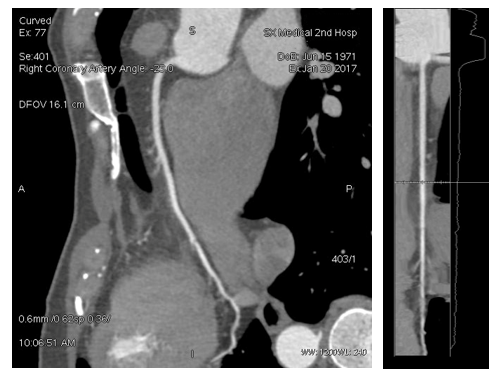

在此期间,山医大二院参照中国胸痛中心总部认证标准,于2月27日正式成功成立山西省的又一个“胸痛中心”,并加快新的介入机房建设和人员配备,向着省内首家胸痛管理中心的目标迈进。急性胸痛起病急、进展快、死亡率高,多发于青壮年。对于急性胸痛的救治,要求迅速做出诊断,进而采取有效措施,可以降低死亡率。Revolution CT在胸痛三联的扫描中具有独特的优势,“一站式”即可完成三联成像,扫描简便易行。“一次打药就可以使冠状动脉、肺动脉以及主动脉均获得显示,并达到很好的图像质量,且扫描时间较传统CT更快,患者接受的射线剂量大幅减少,含碘造影剂的使用量与单部位扫描相当。” 病例二:胸痛三联检查